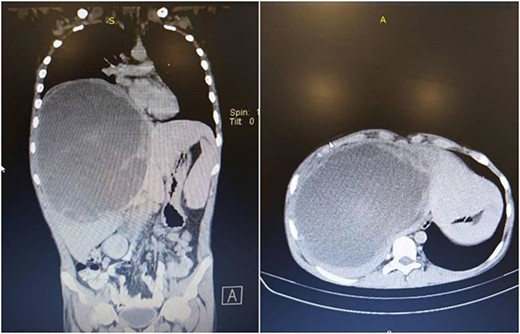

A computerized tomography (CT) scan of the chest, abdomen, and pelvis with intravenous contrast medium confirmed the presence of this giant heterogeneous mass, with a diameter of 15 cm, located in the right lobe of the liver (segment 4a, 4b, 5, 6, 7, 8), with clear margins, non-homogeneous density, that does not contain obvious calcifications. It showed peripheral enhancement with delayed central nodular enhancement without accompanying cysts. No dilation was observed in the biliary or portal ducts. There was a mild reactive pleural effusion with no evidence of secondary pulmonary or hepatic lesions (Fig. 1).

Chest, abdomen, and pelvis CT scan showed a giant heterogeneous mass in the right lobe of the liver.